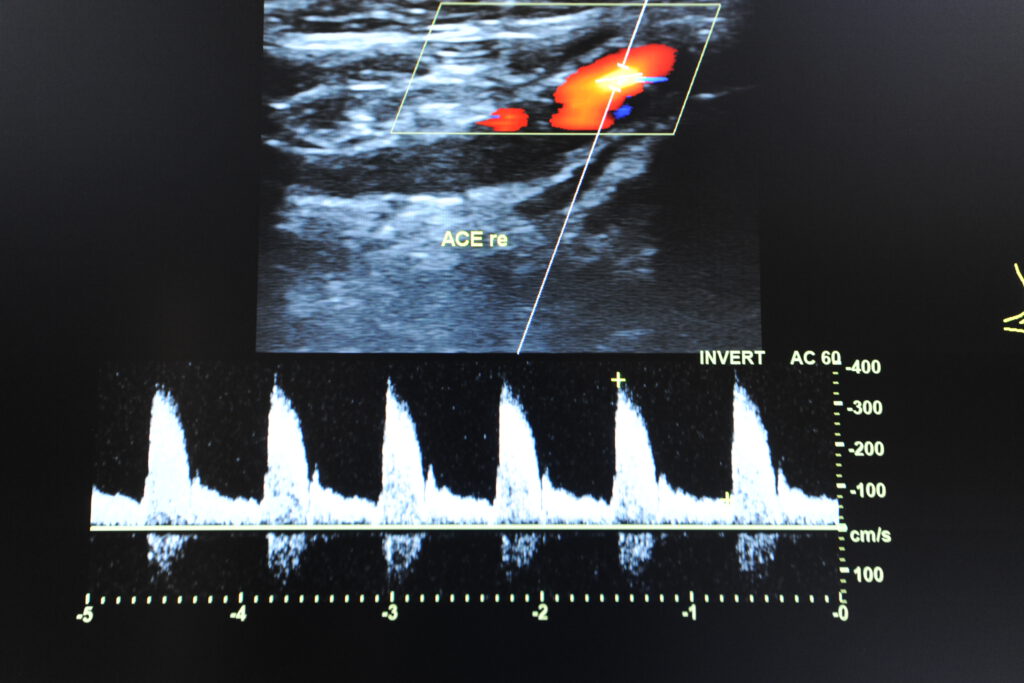

– Ultraschalluntersuchungen (Echokardiografie) von Herz,

Halsgefäßen,

- Kardio-Check (ausgiebige Anamnese, körperliche Untersuchung, Ultraschall von Herz, hirnversorgende Gefäße, EKG, ggf. Belastungs EKG

- Komplett-Check: (ausgiebige Anamnese, körperliche Untersuchung, Hautkrebsscreening, Stuhluntersuchung auf Mikroblutungen, Urinuntersuchung, grosse Blutuntersuchung, Ultraschall vom Bauch, Herz, hirnversorgende Gefäße, Schilddrüse, Lungenfunktionsuntersuchung, EKG, ggf. Belastungs EKG)